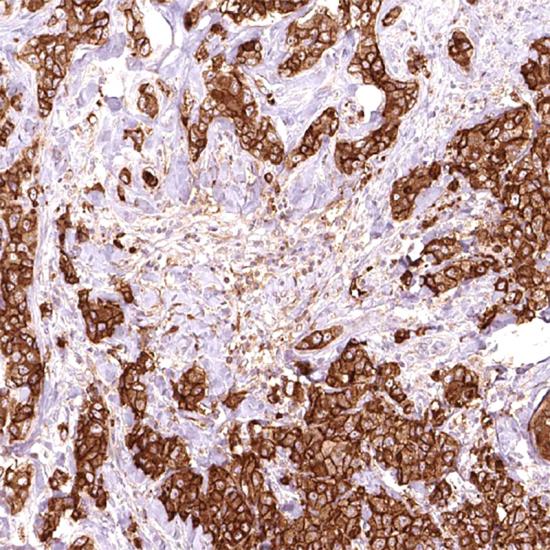

MUC-1

MUC-1抗體試劑(免疫組織化學(xué)) 閩廈械備20180258號(hào)

粘蛋白(MUC-1)是一組高分子量的穿膜糖蛋白,表達(dá)于大多數(shù)的分泌上皮,包括乳腺上皮和一些造血細(xì)胞。MUC-1廣泛表達(dá)于分泌乳汁的乳腺中,在90%以上的乳腺癌中過表達(dá)。MUC-1在許多良性漿液性腫瘤中有表達(dá),而在良性粘液性腫瘤中表達(dá)量下降;在惡性腫瘤中,通常在腺癌以及漿液性和粘液性腫瘤的交界處有表達(dá)。MUC-1和MUC-2同時(shí)表達(dá)與卵巢粘液性腫瘤的惡性度相關(guān)。